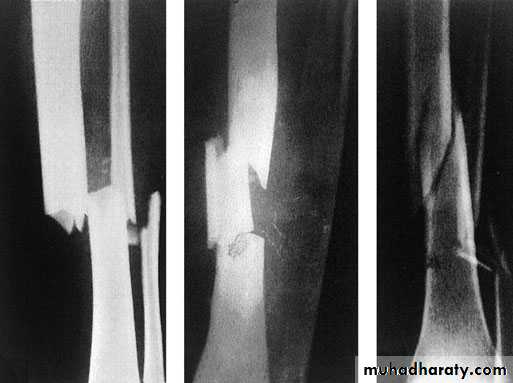

The x- ray pattern may suggest the dominant mechanism:

Twisting cause spiral fractureCompression cause short oblique fracture

Bending cause fracture with triangular butterfly fragment.

Tension cause transverse fracture

Transverse segmental spiral Greenstick fracture